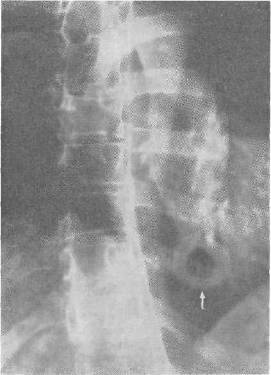

Рис. 18. Грыжа мечевидного отростка у больной 53 лет.

В случае обследования больных с жалобами на боли в подложечной области необходимо при собирании анамнеза уточнить локализацию и характер болевых ощущений и выявить участки наибольшей болезненности. Ощупывание мечевидного отростка значительно затрудняется при избыточно развитом подкожножировом слое. Рентгенография может выявить дефект в мечевидном отростке. В случае Т. Юсупова у женщины 53 лет на рентгенограмме отчетливо было видно отверстие в мечевидном отростке со склерозированными краями, диаметр отверстия 1 см (рис. 18).